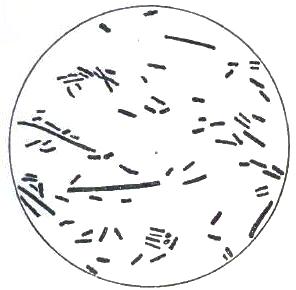

| FIGURE | |

| 1. | MICROCOCCI |

| 2. | BACTERIA |

| 3. | BACILLUS MALARIÆ |

| 4. | BACTERIA FROM GELATIN SOLUTION |

| 5. | VIBRIOS IN GELATIN CULTURE-FLUID |

| 6. | PROTOCOCCUS FROM SLIDES EXPOSED OVER SWAMP-MUD |

| 7. | BACILLI FROM SWAMP-MUD |

| 8. | BACILLI FROM SEPTICÆMIC RABBIT |

| 9. | BACILLI FROM HUMAN SALIVA |

| 10. | BACILLUS ANTHRACIS |

| 11. | BACILLUS TUBERCULOSIS |